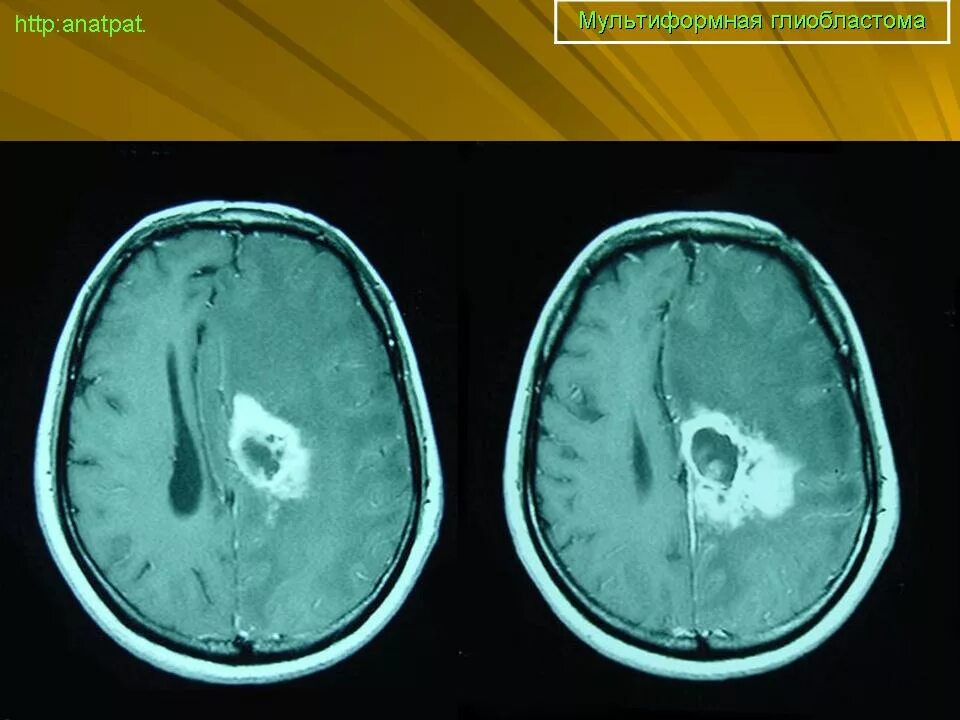

Мрт симптомы